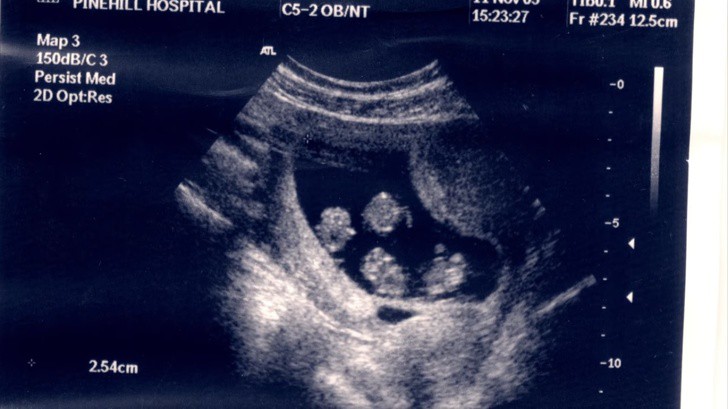

Trong buổi khám thai đầu tiên, hình ảnh 4 phôi thai trong tử cung người mẹ đã khiến mọi người vô cùng bất ngờ.

Và điều ngạc nhiên hơn nữa đã được tiết lộ trong buổi khám thai đầu tiên. Sau khi siêu âm và cầm trên tay bức ảnh chụp đầu tiên của em bé, Julie đã vô cùng bất ngờ khi bác sĩ thông báo Julie đang mang đa thai. Tuy nhiên, hai vợ chồng chỉ mỉm cười và nghĩ về một cặp song sinh. Nhưng không ai ngờ rằng thực tế có đến 4 đứa trẻ đang cùng lớn lên trong bụng Julie. Điều này không chỉ khiến cặp đôi choáng váng mà các bác sĩ chuyên khoa cũng khẳng định đây là trường hợp vô cùng hiếm gặp với những ca thụ thai 4 tự nhiên.